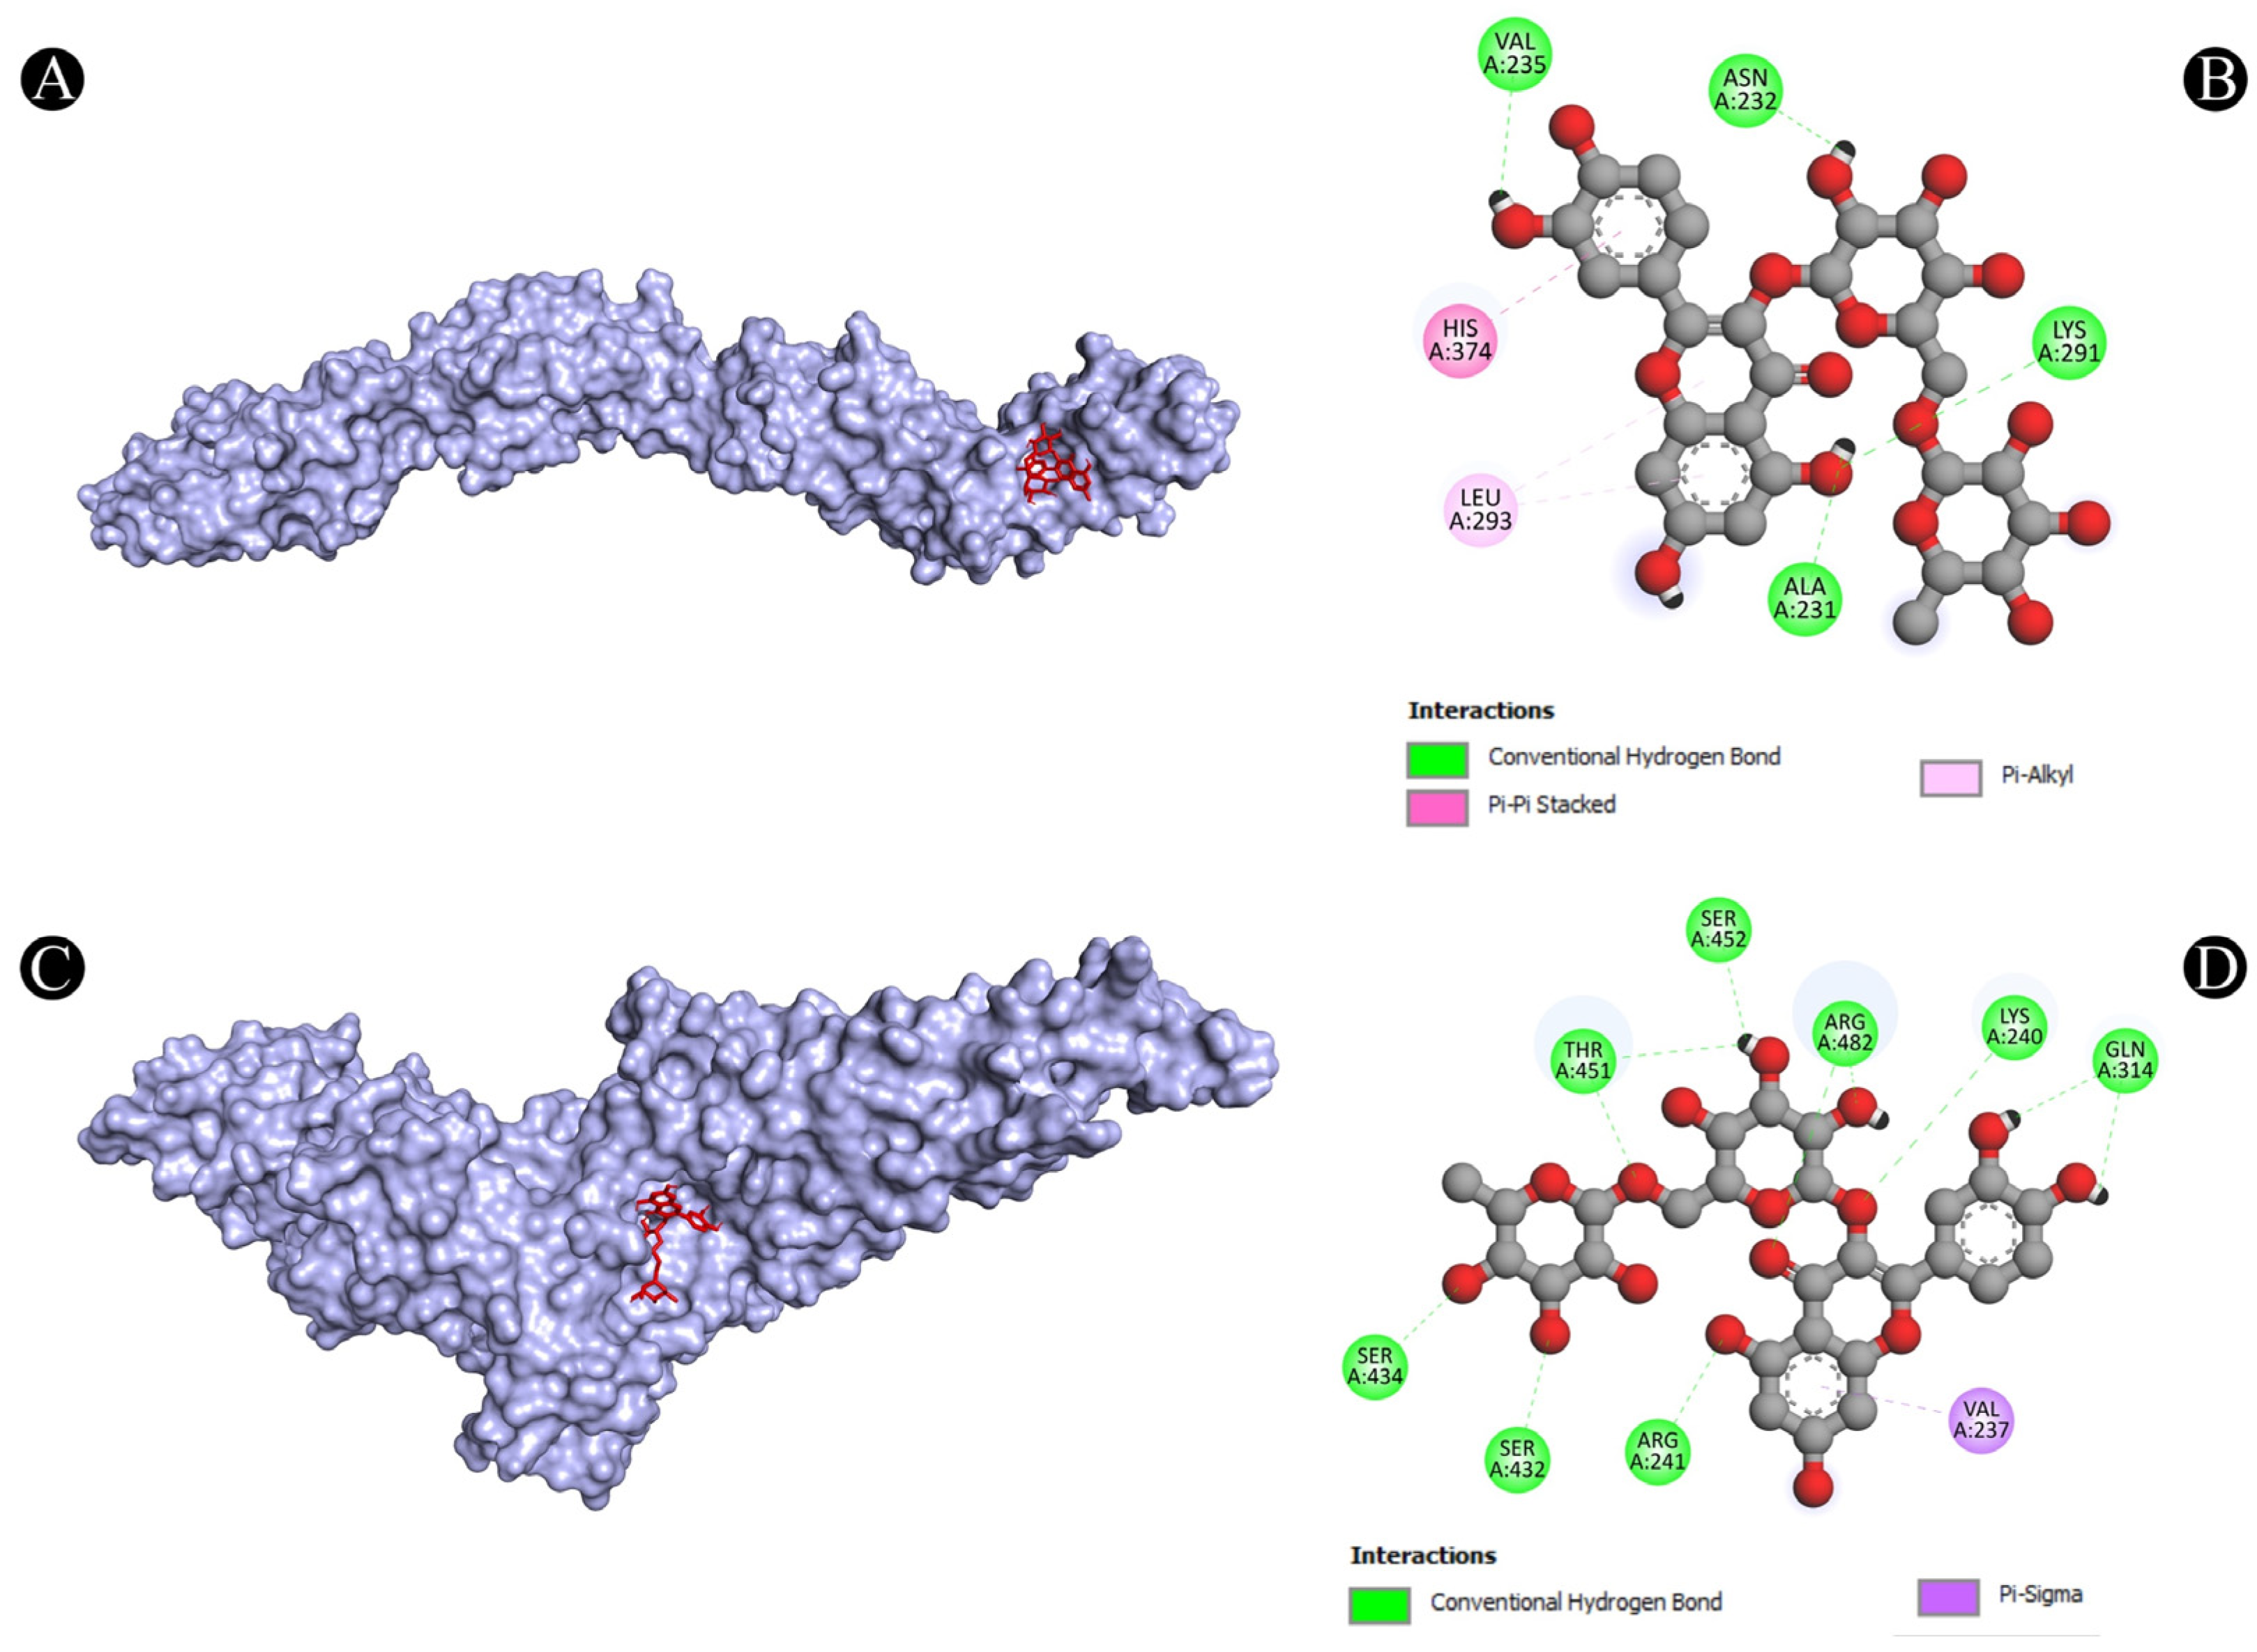

3.4. Molecular Docking Analysis

| 4 | PTPRC | A:LYS291:HZ1-N:UNK1:O | Conventional Hydrogen Bond | 2.49711 |

| N:UNK1:H-A:VAL235:O | Conventional Hydrogen Bond | 2.70571 | ||

| N:UNK1:H-A:ALA231:O | Conventional Hydrogen Bond | 2.54842 | ||

| N:UNK1:H-A:ASN232:O | Conventional Hydrogen Bond | 2.57383 | ||

| A:HIS374-N:UNK1 | Pi-Pi Stacked | 4.36158 | ||

| N:UNK1-A:LEU293 | Pi-Alkyl | 5.26513 | ||

| N:UNK1-A:LEU293 | Pi-Alkyl | 5.26961 | ||

| 5 | STAT1 | A:LYS240:HZ3-N:UNK1:O | Conventional Hydrogen Bond | 2.11392 |

| A:ARG241:HH11-N:UNK1:O | Conventional Hydrogen Bond | 2.78186 | ||

| A:ARG241:HH21-N:UNK1:O | Conventional Hydrogen Bond | 1.92015 | ||

| A:SER432:HG-N:UNK1:O | Conventional Hydrogen Bond | 2.58764 | ||

| A:SER434:HG-N:UNK1:O | Conventional Hydrogen Bond | 2.76816 | ||

| A:THR451:HG1-N:UNK1:O | Conventional Hydrogen Bond | 3.06789 | ||

| A:ARG482:HH11-N:UNK1:O | Conventional Hydrogen Bond | 2.16428 | ||

| A:ARG482:HH11-N:UNK1:O | Conventional Hydrogen Bond | 3.0504 | ||

| A:ARG482:HH21-N:UNK1:O | Conventional Hydrogen Bond | 2.62021 | ||

| N:UNK1:H-A:GLN314:O | Conventional Hydrogen Bond | 2.12922 | ||

| N:UNK1:H-A:GLN314:O | Conventional Hydrogen Bond | 2.11387 | ||

| N:UNK1:H-A:THR451:O | Conventional Hydrogen Bond | 2.07658 | ||

| N:UNK1:H-A:THR451:OG1 | Conventional Hydrogen Bond | 2.24927 | ||

| N:UNK1:H-A:SER452:O | Conventional Hydrogen Bond | 2.74446 | ||

| A:VAL237:CG2-N:UNK1 | Pi-Sigma | 3.65444 | ||

| PTPRC (protein tyrosine phosphatase receptor type C) | Regulates T cell receptor signaling and immune response against fungal infection | PTPRC, also known as CD45, is a protein that can regulate the signaling of T cell receptor (TCR), which is a molecule that recognizes antigens presented by infected cells. PTPRC can modulate the activation and differentiation of T cells and their anti-fungal effector functions. Ajwa date extract may stimulate the release of PTPRC and improve its anti-fungal function. | [71,72] |

| STAT1 (signal transducer and activator of transcription 1) | Activates anti-fungal genes and enhances the phagocytosis of fungal cells | STAT1 is a transcription factor that can activate the expression of genes that are involved in anti-fungal responses, such as IFN-gamma, NOS2 and CXCL10. STAT1 can also enhance the phagocytosis of fungal cells by macrophages, which are immune cells that can engulf and destroy foreign particles. Ajwa date extract may stimulate the release of STAT1 and increase its anti-fungal function. | [90,92] |